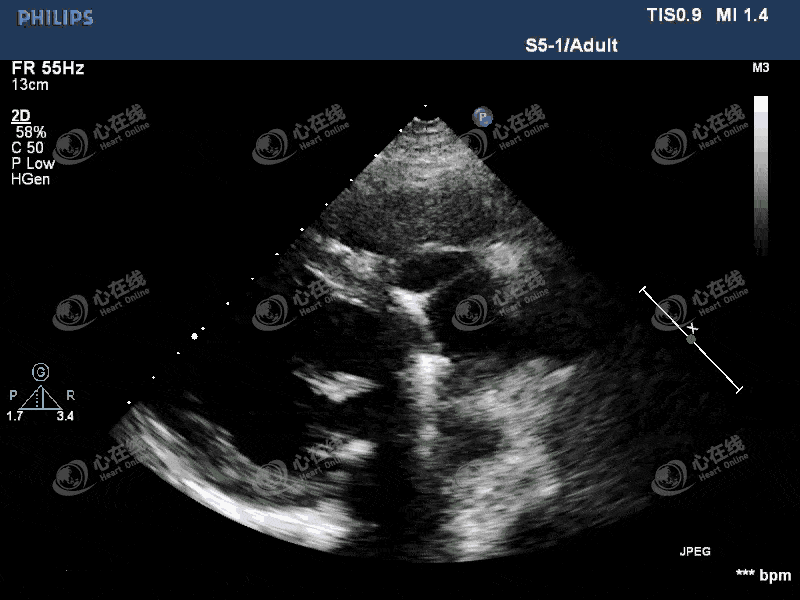

心脏动态图超声

心肌梗塞的超声表现